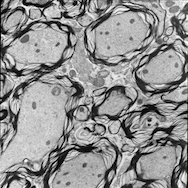

5.3.2 Image Analogies Results

We tested the original image analogy method and our proposed method on correlative microscopy images. For each test dataset, I train the dictionaries based on two randomly selected image pairs. We can also train the dictionaries based on more datasets at increased computational cost. In both image analogies methods I use 15×15151515\times 15 patches, and in our proposed method I randomly sample 100001000010000 patches and learn 900900900 dictionary elements in the dictionary learning phase. We choose γ=0.01𝛾0.01\gamma=0.01 and λ=1𝜆1\lambda=1 in (7). The learned dictionaries for both TEM and confocal images are displayed in Fig. 6. The image analogies results in Fig. 7 show that our proposed method preserves more local coherence than the original image analogies method.

Refer to caption

(a) case 1: TEM image

(b) Registered confocal image

(c) Original IA result

(d) Proposed IA result

(e) case 2: TEM image

(f) Registered confocal image

(g) Original IA result

(h) Proposed IA result

Figure 7: Result of Image Analogies (IA)

(q) case 5: TEM image

(r) Registered confocal image

(s) Original IA result

(t) Proposed IA result

(u) case 6: TEM image in Case 6

(v) Registered confocal image

(w) Original IA result

(x) Proposed IA result

Figure 7: Result of Image Analogies Cont’d